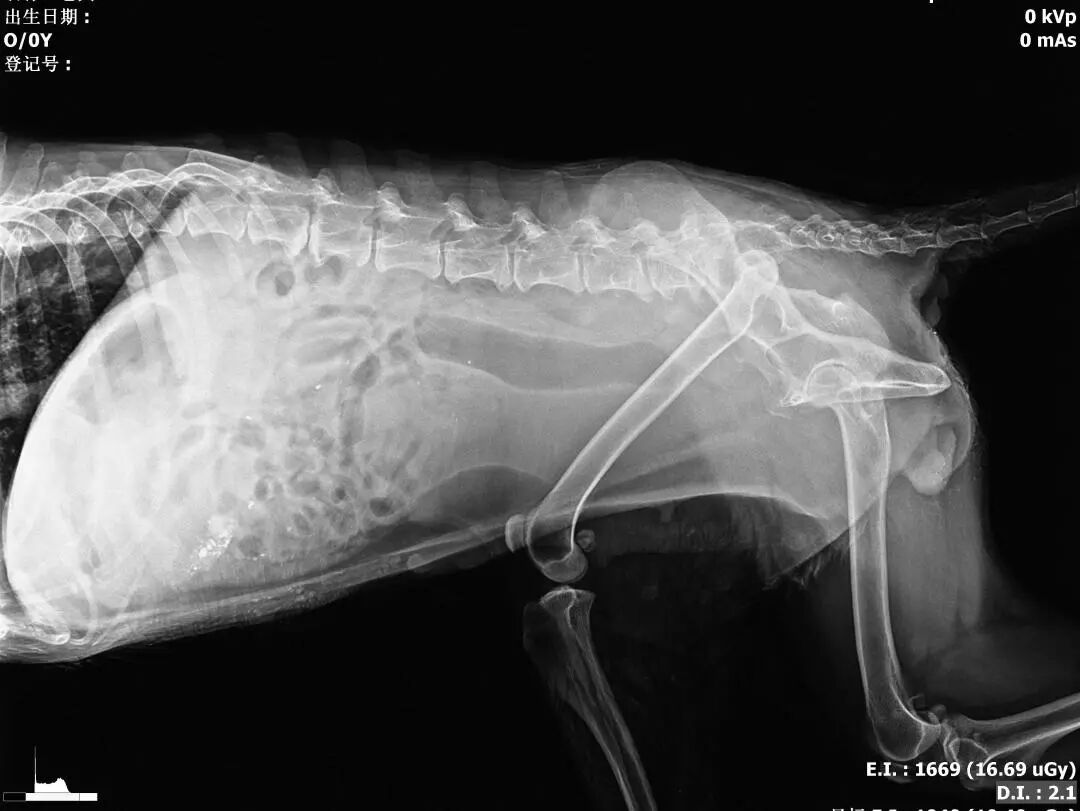

2、血常规、生化、凝血、DR(正侧)

动物拍片腹部怎么摆【病例分享】犬-外科-股骨头切除术_https://www.jmylbn.com_新闻资讯_第7张

术后侧位片

动物拍片腹部怎么摆【病例分享】犬-外科-股骨头切除术_https://www.jmylbn.com_新闻资讯_第31张